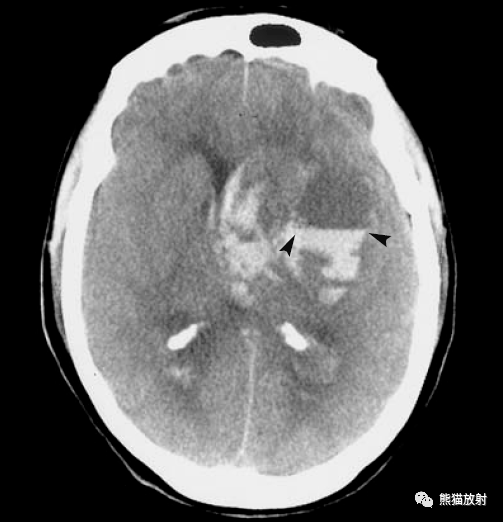

脑实质内出血的演变,分布,ct表现

由海绵状血管瘤破裂引起的iph.22岁女性,内囊后肢局部出血性病变.